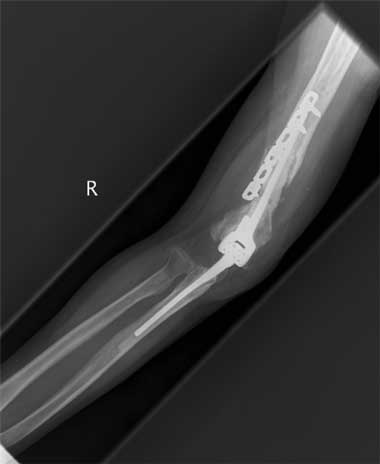

All 11 patients were taken to theatre within 24 hours of arrival at RPH and all underwent a washout and debridement. Depending on the injury, the procedures performed included open reduction and internal fixation; nerve, artery and tendon repair; and free flaps and split-skin grafting. Nine patients underwent multiple surgical procedures; 10 required open reduction and internal fixation with low contact dynamic compression plates for open fractures of the humerus, ulna and radius. The various plating procedures are illustrated in Box 2.

The most severe upper-arm injury involved Patient 7, with loss of the right distal humerus and olecranon, combined with an ulna nerve injury (Box 3). Initial treatment consisted of debridement and application of a bridging external fixator across the lost elbow joint (Box 4). This was complicated by iatrogenic radial nerve neuropraxia caused by the insertion of a Steinman pin. The external fixator was later replaced by a humeral allogeneic bone graft, an elbow prosthesis, and plate fixation of the humeral shaft (Box 5). The same patient also subsequently underwent a revision of the humeral plate procedure after a deep infection with Staphylococcus epidermidis was identified.